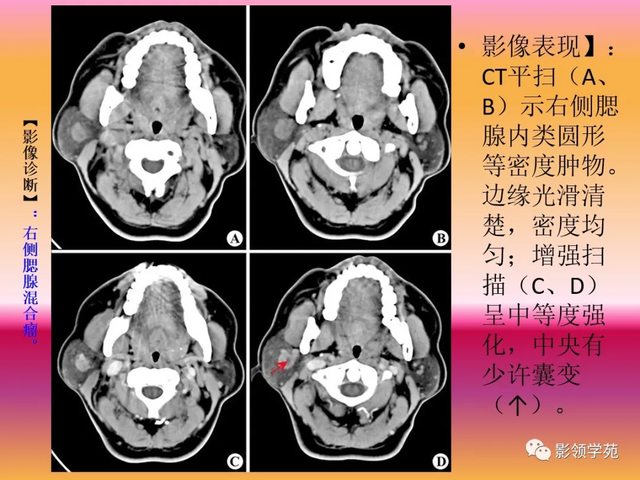

病例3:男性,68岁,因“发现右耳垂下肿物30余年”:

病理:腺淋巴瘤

病例4:男性,81岁,因发现右耳下肿物10年余,举行 性增大2年: